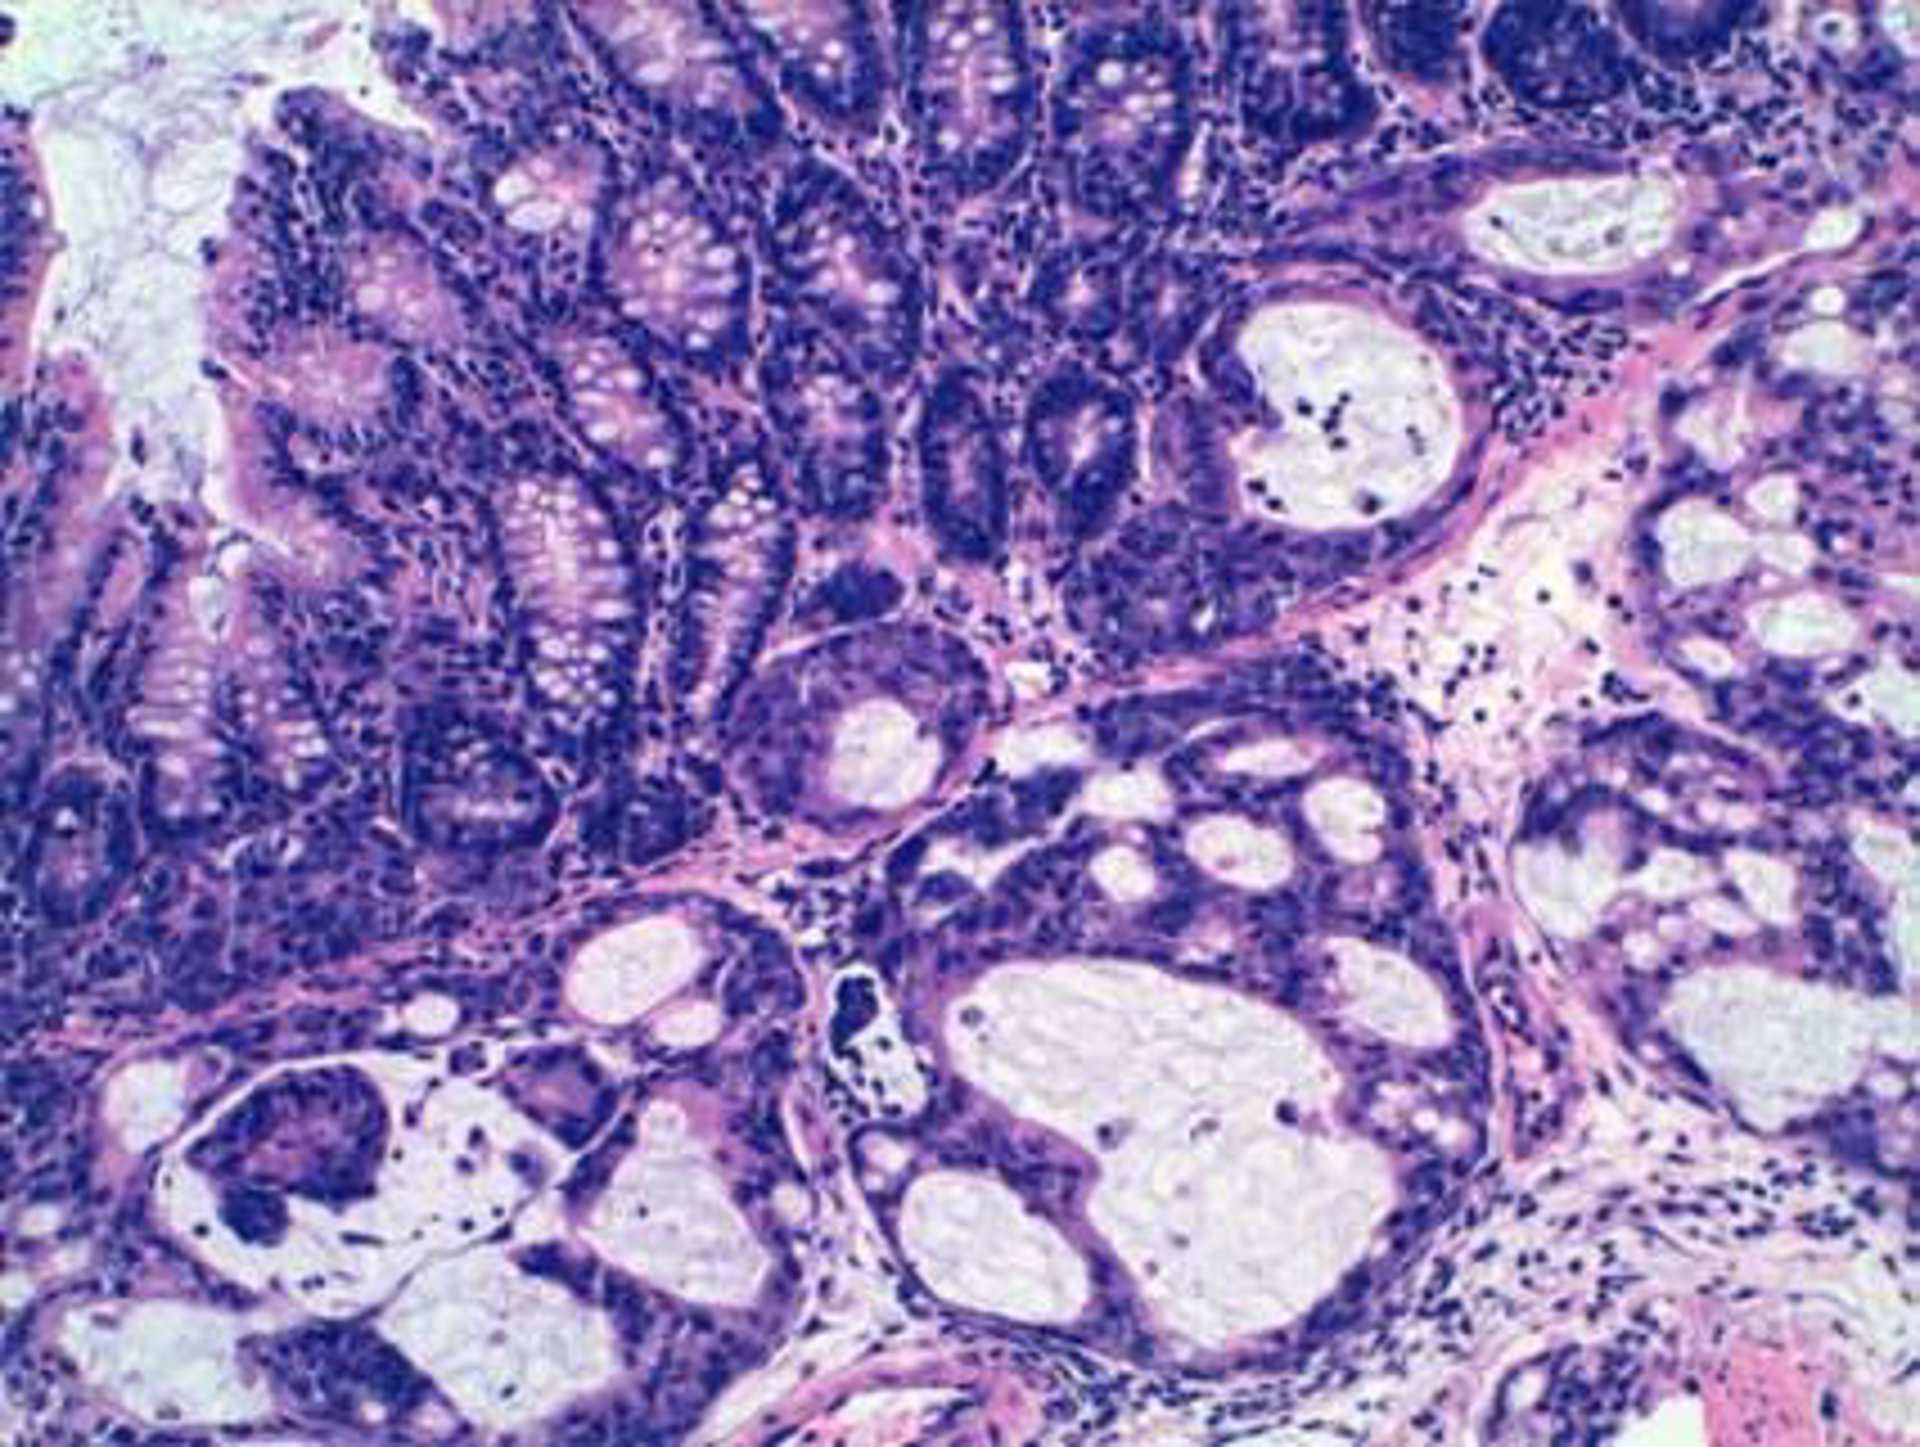

Tumor de colon cuyo crecimiento está inhibico con enoxacina